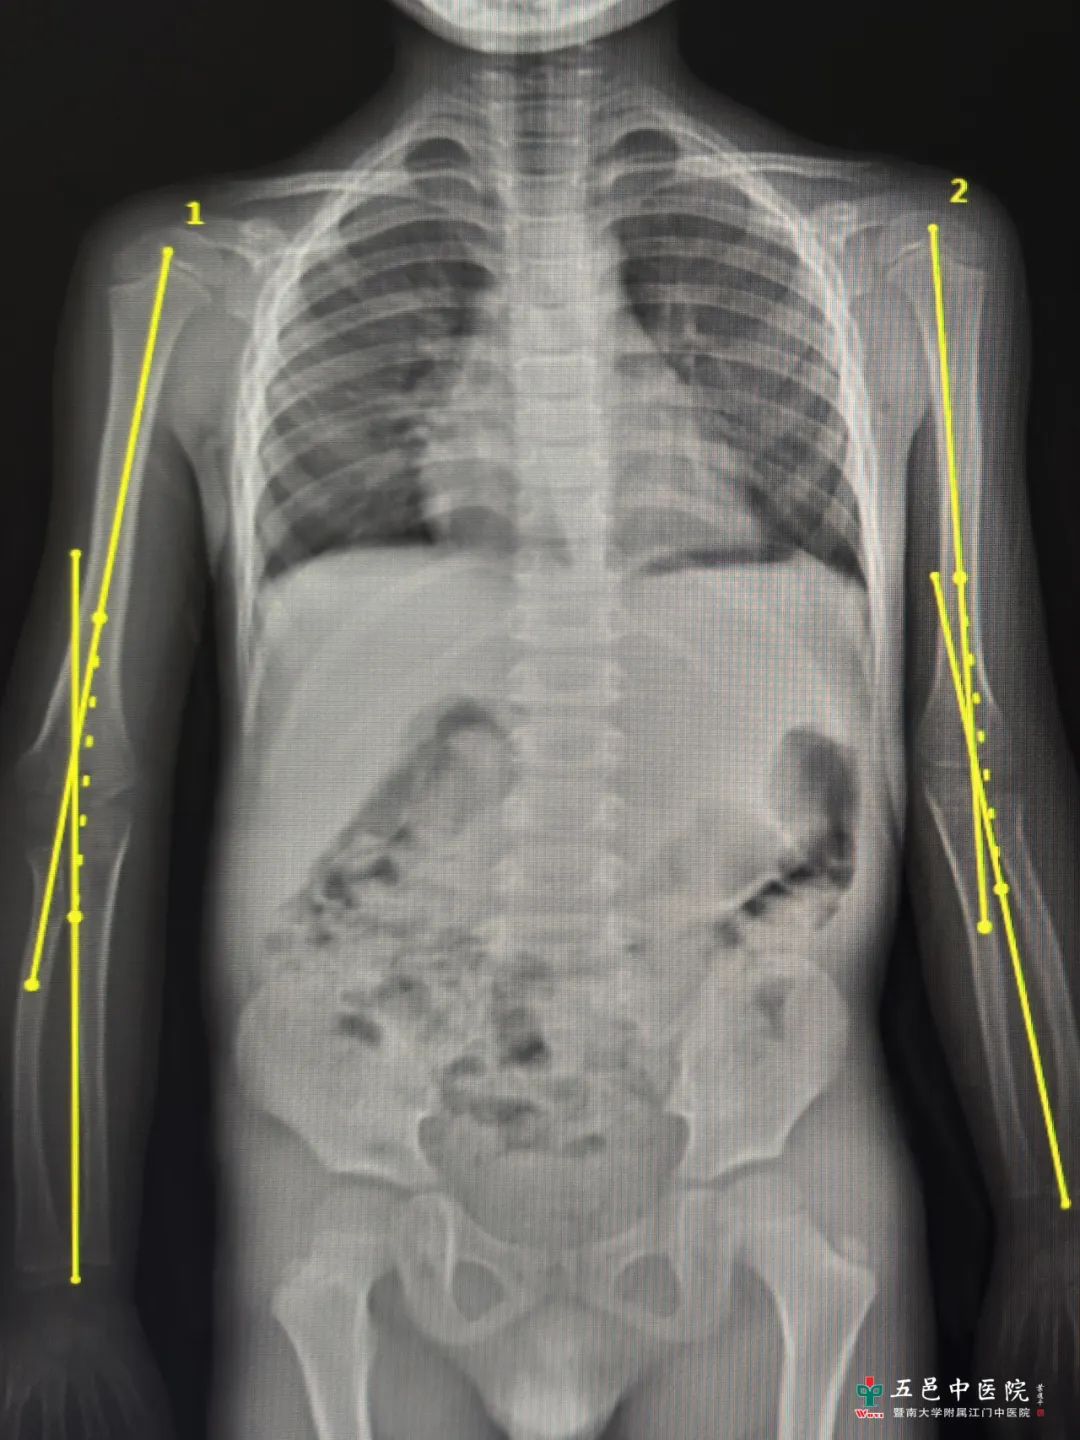

术前双上肢正位DR